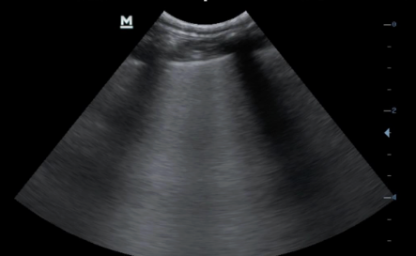

Best site to find smaller volumes of pleural effusion on ultrasound

Between caudal heart and cranial liver

Also cranial to heart

How do you rule out pneumothorax at a site being ultrasounded?

Glide sign = shimmering white lines that move laterally

What are these lines?

B lines → something is wrong within 1mm periphery of the lung